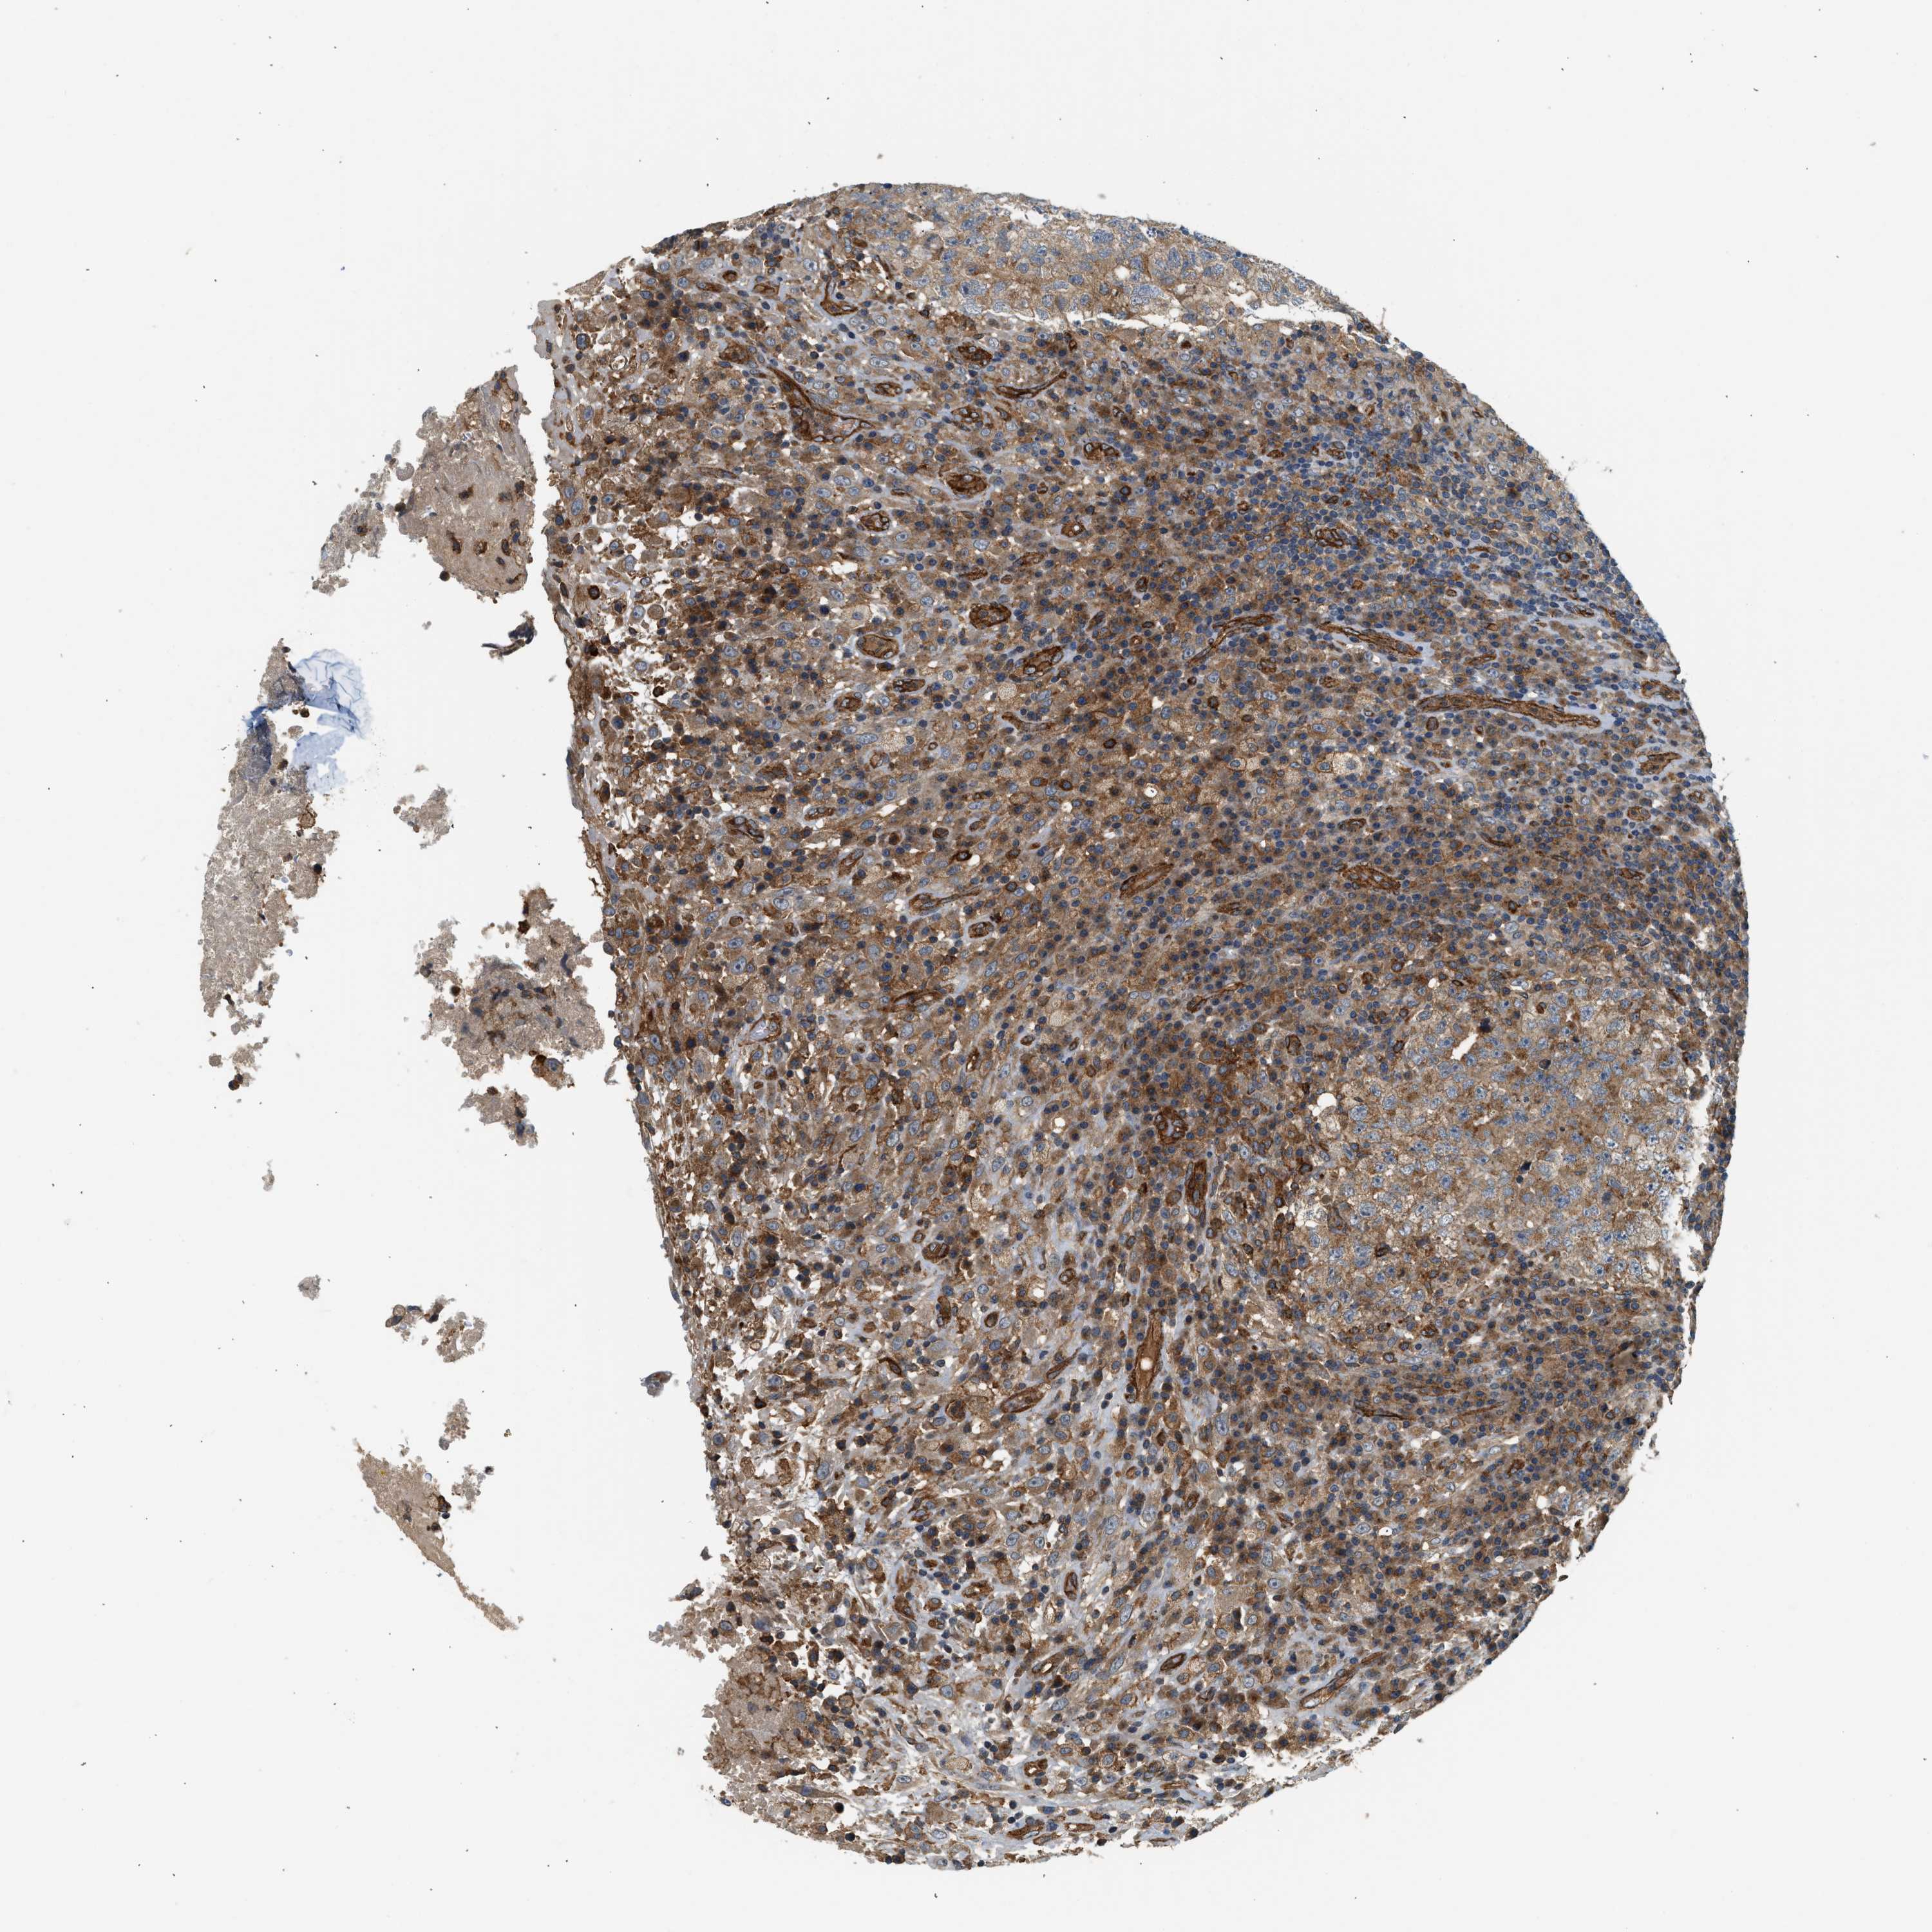

TESTIS CANCER - Protein expressioni

A mouse-over function shows sample information and annotation data. Click on an image to view it in a full screen mode. Samples can be filtered based on level of antibody staining by selecting one or several of the following categories: high, medium, low and not detected. The assay and annotation is described here.

Note that samples used for immunohistochemistry by the Human Protein Atlas do not correspond to samples in the TCGA dataset.

Antibody stainingi

Antibody staining in the annotated cell types in the current human tissue is reported as not detected, low, medium, or high, based on conventional immunohistochemistry profiling in selected tissues. This score is based on the combination of the staining intensity and fraction of stained cells.

Each image is clickable and will lead to virtual microscopy that enables deeper exploration of all samples and also displays staining intensity scores, fraction scores and subcellular localization as well as patient and tissue information for each sample.

Antibody HPA013606

Antibody CAB015334

Staining

High

Medium

Low

Not detected

Intensity

Strong

Moderate

Weak

Negative

Quantity

>75%

75%-25%

<25%

None

Location

Nuclear

Cytoplasmic/membranous

Cytoplasmic/membranous,nuclear

Carcinoma, Embryonal, NOS

Seminoma, NOS